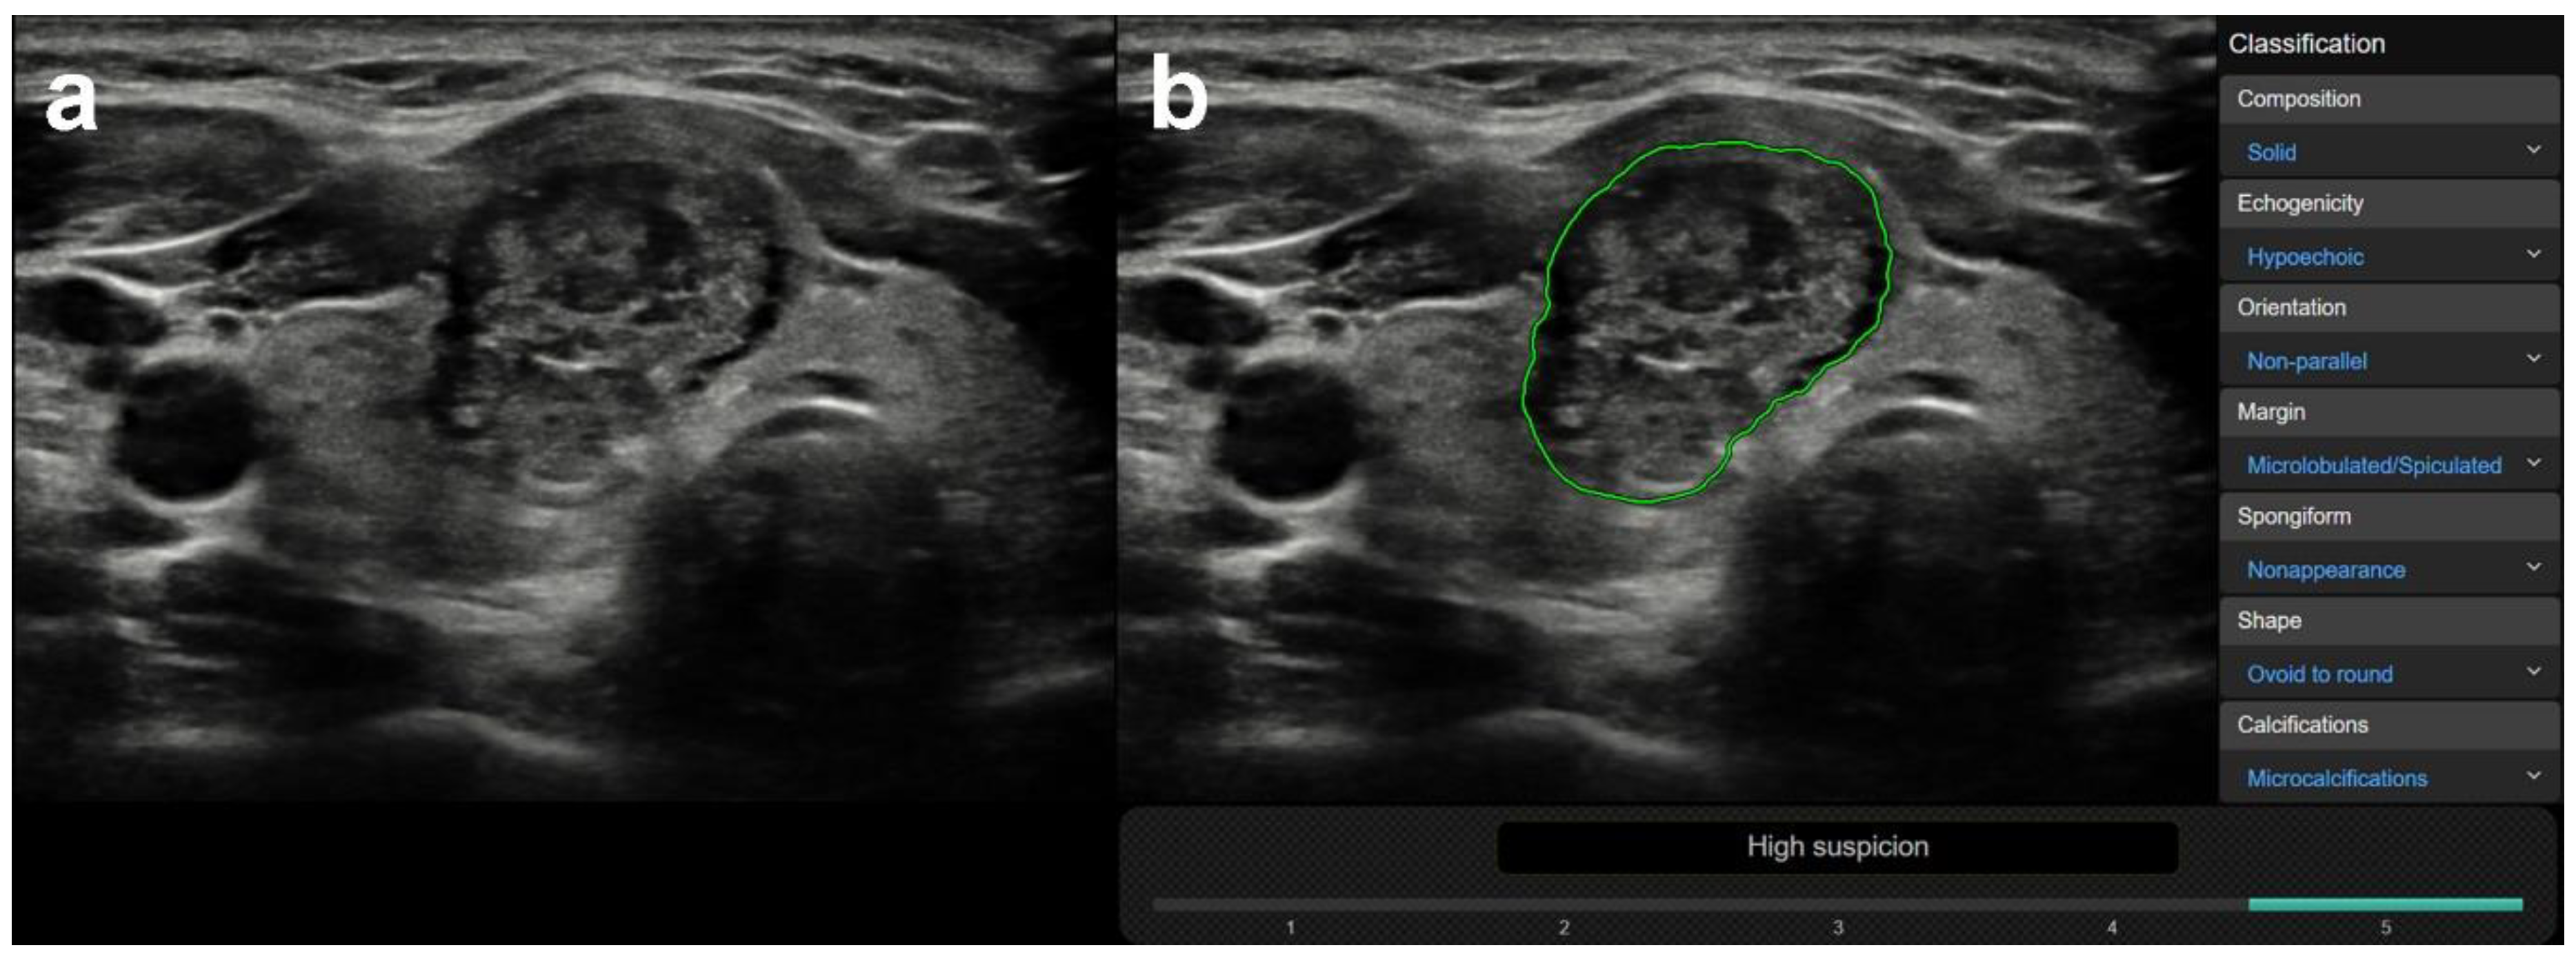

3.1. US Features or Entities Associated with CAD System Misdiagnosis Including Mimicking Lesions